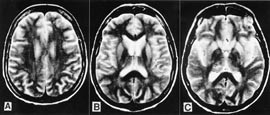

Pasienten. 54 år gammel kvinne. Hun hadde tidligere stort sett vært frisk, men gjennomgikk flere tannekstraksjoner og maksillærkirurgi det siste året før sykdomsdebut. De første symptomene var svimmelhet, asteni og vertigo, som tiltok gradvis. Åtte måneder senere utviklet hun ustø gange, eufori og raskt progredierende demens med desorientering, tap av korttidsminne og visuelle hallusinasjoner. Ved klinisk undersøkelse fant man nystagmus, ataksi, myoklonus, positiv mandibular og palmomental refleks og grav demens. Computertomografi (CT) av hjernen og blodprøver viste normale funn. EEG viste diffus dysrytmi med generalisert theta- og deltaaktivitet, men de typiske periodiske skarpe bølger som vanligvis sees ved Creutzfeldt-Jakobs sykdom, var ikke til stede. T2-vektet MR av hjernen viste ingen definitive avvik (fig 1). Diffusjonsvektet MR av hjernen viste markert økt signaldensitet, dvs. redusert diffusjon bilateralt i corpus striatum og gyrus cinguli (fig 2). Hun døde etter en måned i koma, 15 måneder etter debuten av de første symptomene. Diagnosen ble postmortalt bekreftet med utbredte, typisk spongiforme encefalopatifunn ved den histopatologiske undersøkelsen (fig 3). Prionproteingenanalyse viste ingen mutasjoner, men hun var homozygot for valin/valin i codon 129 (utført ved Creutzfeldt-Jakob Disease Surveillance Unit, Edinburgh, Skottland).

Dette tilfellet av Creutzfeldt-Jakobs sykdom er ett av få hittil rapporterte pasienter (8 – 12) som ble undersøkt med diffusjonsvektet MR. De patologiske forandringene man ser i diffusjonsvektet MR, er tydelige hyperintense signalavvik i basale ganglier og/eller cortex cerebri. Disse forandringene, som representerer redusert diffusjon grunnet funksjonsforstyrrelser i de aktuelle hjernedelene, ser ut til å være karakteristiske for Creutzfeldt-Jakobs sykdom. Det finnes ikke andre rapporterte tilstander med liknende diffusjonsforandringer. Diffusjonsvektet MR kan derfor være en undersøkelse som gir spesifikke funn for Creutzfeldt-Jakobs sykdom, og et nytt instrument i den premortale diagnostikken av denne sykdommen.